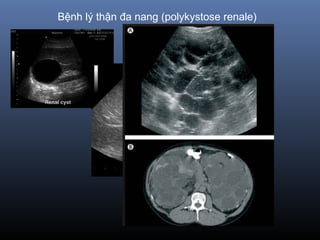

 B nh lý Th n đa nang (polykystose renale)ệ ậ

lan chi m toàn b th nế ộ ậ

Bệnh lý thận đa nang (polykystose renale)